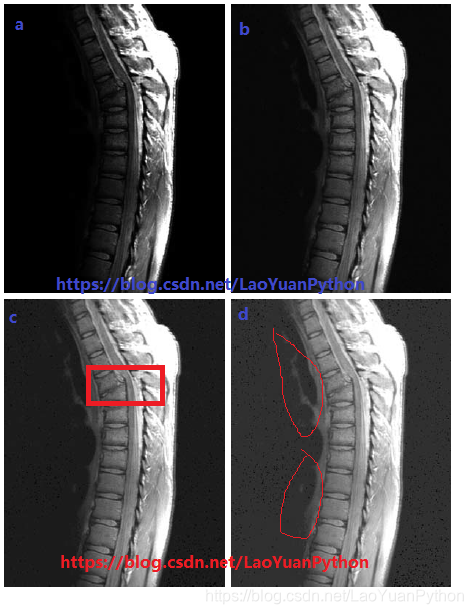

下图a为一幅核磁共振图(MRI,magnetic resonance image),图中显示了人体胸部以上脊椎骨折错位和脊髓收到影响的情况,骨折位置在胸椎垂直中心附近(图中从上往下约1/4处):

图像a整体偏暗,需要通过扩展灰度级提升对比度,用γ值分别为0.6、0.4、0.3对a图进行幂律变换,得到b、c、d三图。可以看到随着γ值的减小,更多的细节变得可见了,而0.3的γ值,背景中的细节有很小的进一步增强,但图像有轻微“褪色(washed-out)”的外观,特别是背景中老猿用红笔标记之处。在这幅图像中,γ=0.3是个近似的极限点,再低于该值对比度会下降到令人难以接受的程度。

注:骨折这个地方找了半天不能确认,老猿认为是C图中红色框范围内那处,请别人帮忙也不能确认。另外褪色的部分标记也是老猿自己理解的,不能确保是否正确,请大家自行理解。